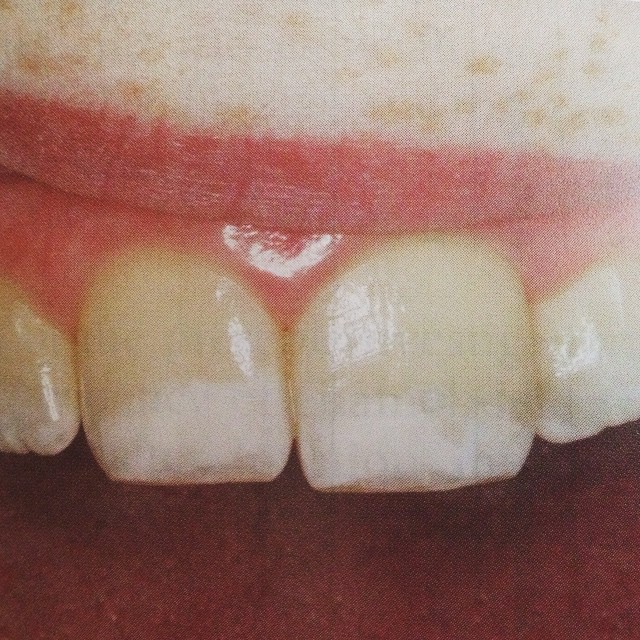

Местная Гипоплазия

детская стоматологияЧто это за белые пятна на зубах❓в данном случае речь идет о так называемой местной гипоплазии двух центральных зубов.. Что это такое? Почему она возникает? И, самое главное, это лечится и как?

Гипоплазия твердых тканей зуба это некое недоразвитие, которое возникло в момент формирование зуба еще до его прорезывания. Причинами такой ситуации может стать: 1⃣ травма молочного зуба, ранее стоявшего на этом месте 2⃣непролеченные молочные зубы, ранее стоявшие на этом месте 3⃣пролеченные те же самые зубы, но не во время, когда воспаление уже вышло за пределы зуба и повлияло на зачаток постоянного зуба. На фото самая безобидная форма проявления данного заболевания - изменение цвета.. Существуют большие риски изменения структуры зуба. По поводу лечения.. Прежде всего очень важно донести до ребенка, что его зубки, к сожалению, достаточно слабые и их нечистка чревата последствиями. Поэтому первым и очень важным пунктом в лечении данного заболевания - не допустить присоединения кариеса, который обязательно появится и будет чрезмерно агрессивен, если зубы не чистить, делать это нерегулярно или некачественно. Также необходимо регулярное использование кальцийсодержащими реминерализирующих гелей в домашних условиях. Помимо этого необходим курс реминерализирующей терапии в условия стоматологического кабинета раз в три месяца минимум.. В некоторых случаях и чаще. Что же касается эстетитки⁉️ все это исправляется и приводится в должный вид путем реставрационных работ пломбировочным материалом, но не ранее, чем через 2 года после прорезывания таких зубов..#детскийстоматолог #детскаястоматология #гипоплазиязубов #местнаягипоплазиязубов #детскийстоматологселютина